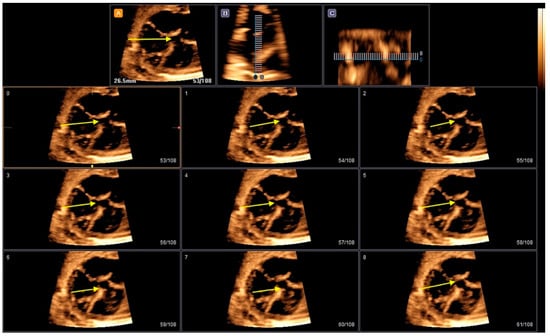

- Rizzo, G.; Capponi, A.; Vendola, M.; Pietrolucci, M.E.; Arduini, D. Role of tomographic ultrasound imaging with spatiotemporal image correlation for identifying fetal ventricular septal defects. J. Ultrasound Med. 2008, 27, 1071–1075. [Google Scholar] [CrossRef]

- Liu, J.; Wang, Y.; Zhao, H.; Liu, W. Spatio-temporal image correlation rendering mode visualizes the specific location and surrounding structure of ventricular septal defect. Clin. Anat. 2019, 32, 408–420. [Google Scholar] [CrossRef]